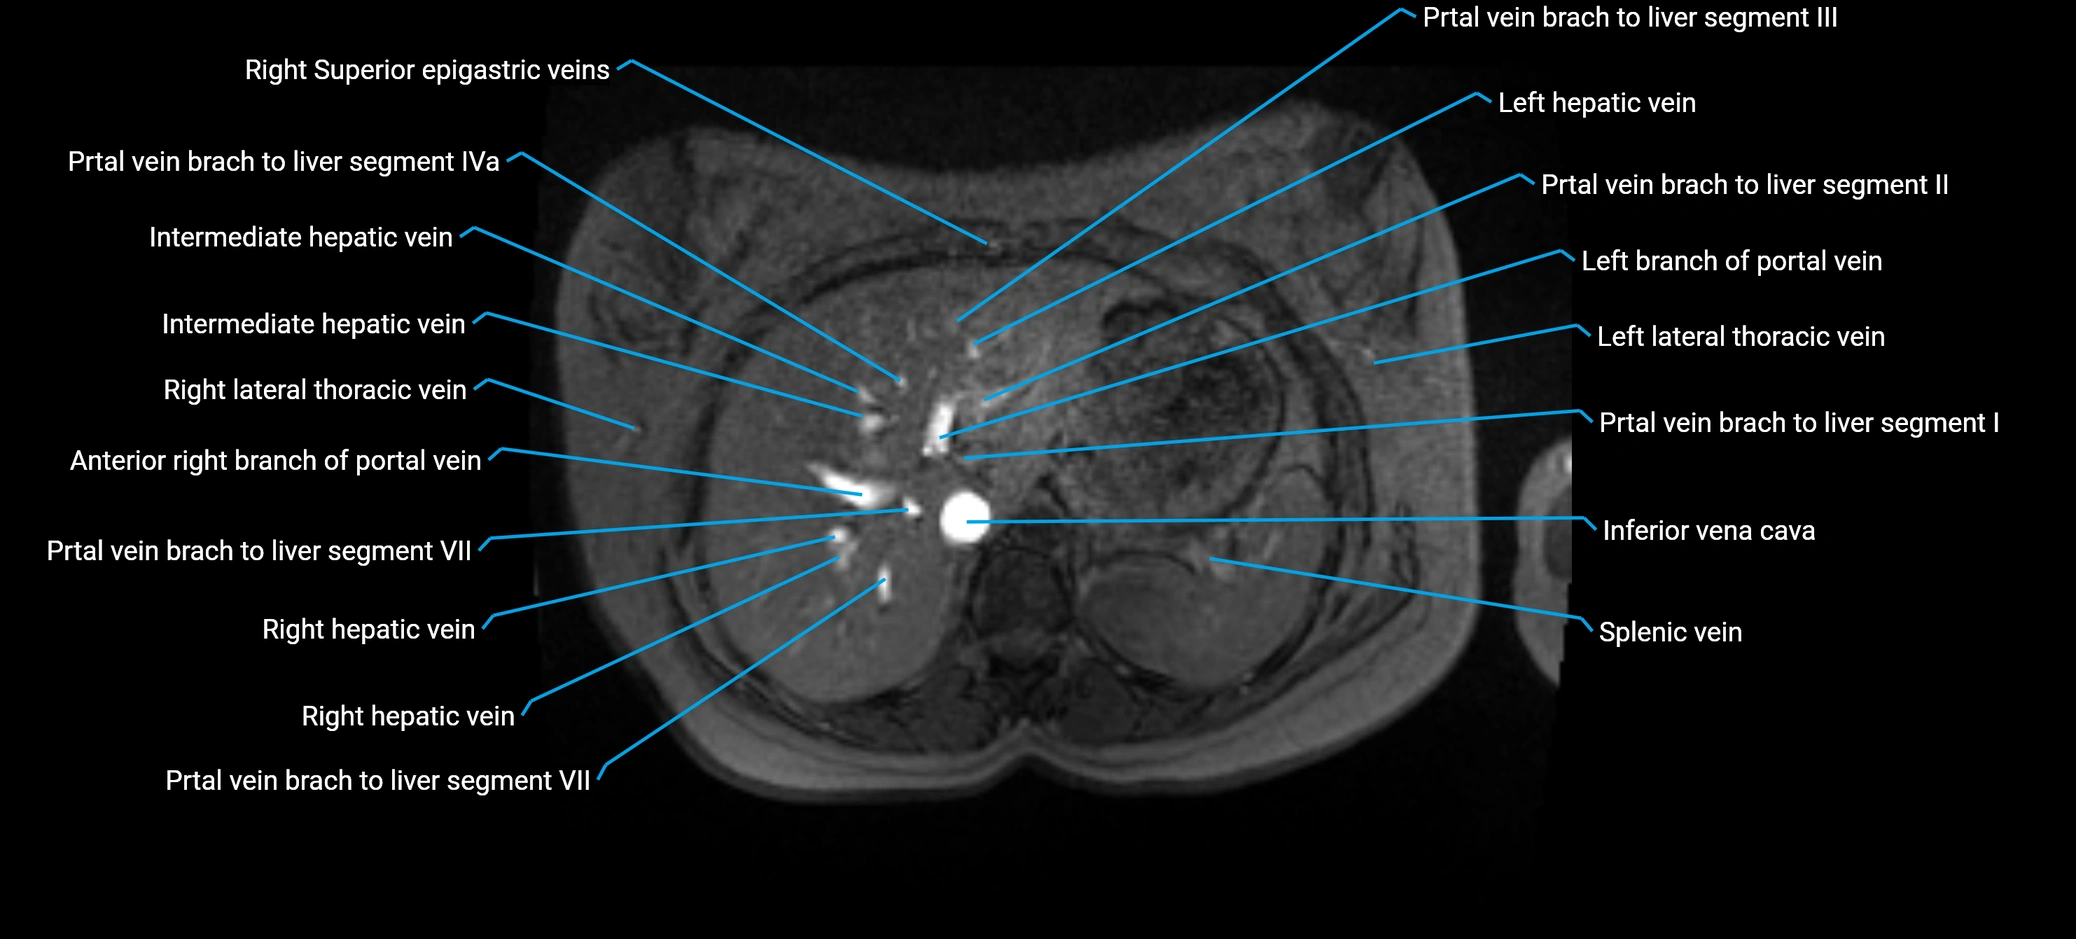

The anterior right branch of the portal vein is a major intrahepatic division of the right portal vein. After the main portal vein bifurcates into right and left branches, the right portal vein divides into anterior and posterior segmental branches.

The anterior right branch supplies the anterolateral liver segments (Segment V) and anteromedial liver segments (Segment VIII) within the right hepatic lobe. It operates as a key vascular route delivering nutrient-rich portal venous blood to the central and superior right liver.

This segmental vasculature is of major importance in hepatic surgery, embolization, segmental resection, transplantation, and imaging-based liver segmentation.

MRV TOF (Time-of-Flight MR Venography):

• Appears as a bright, high-signal vascular channel representing flowing blood

• Clearly shows branching pattern of right portal vein into anterior and posterior branches

• Best in coronal or axial reconstructions for segmental mapping

• No need for contrast, relies on flow-related enhancement

Post-Contrast T1 Fat-Sat GRE:

• Enhances brightly and homogeneously during the portal venous phase

• Clearly delineates branching into segments V and VIII

• Best sequence for evaluating patency, caliber, and anatomic variants

MRI image

image